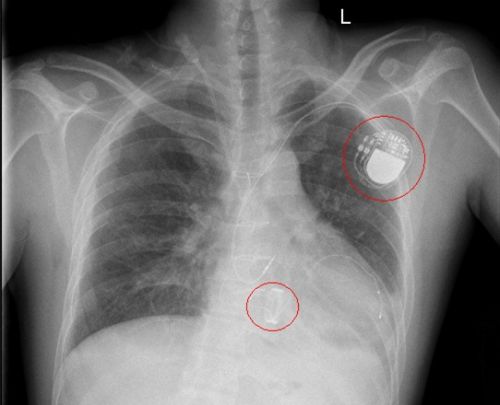

人工心脏起搏器植入术后影像。

待小陈病情稍稳定后,10月20日,心胸外科、心血管内科和呼吸治疗组团队克服重重困难,携带转运呼吸机、心电监护仪、电除颤仪、输液泵等多种仪器设备,前往介入复合手术部为他安装人工心脏起搏器。术后,小陈恢复顺利,于10月26日康复出院。

“这个心脏起搏器将永久停留在他体内,起到提高心室率的作用,相当于心脏的‘充电器’”,杨劲松主任表示,小陈的室速、室颤是长期三度房室传导阻滞引起的。他建议,有心律失常、心率慢病史的人应前往医院进一步检查,如果是病理性的需要及时安装心脏起搏器;出院后,还应在医生指导下定期复查凝血功能、及时更换起搏器电池;瓣膜术后要按时并终身服用抗凝药物;保持良好的生活规律、避免感冒、定期检测起搏器的功能状态。